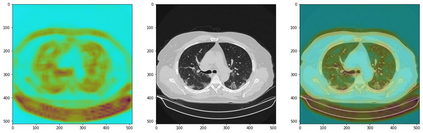

The paper represents a method of a Convolution Neural Networks (CNN) model for image classification with image preprocessing and hyperparameters tuning, aiming at increasing the predictive performance for COVID-19 diagnosis while avoiding deeper and thus more complex alternatives. Firstly, the CNN model includes four similar convolutional layers followed by a flattening and two dense layers. This work proposes a less complex solution based on simply classifying 2D slices of CT scans using a CNN model. Despite the simplicity in architecture, the proposed CNN model showed improved quantitative results exceeding state-of-the-arts on the dataset of images, in terms of the macro F1 score. The results were achieved on the original CT slices of the dataset. Secondly, the original dataset was processed via anatomy-relevant masking of slices, removing non-representative slices from the CT volume, and hyperparameters tuning. For slice processing, a fixed-sized rectangular area was used for cropping an anatomy-relevant region of interest in the images, and a threshold based on the number of white pixels in binarized slices was employed to remove non-representative slices from the 3D-CT scans. The CNN model with a learning rate schedule with exponential decay and slice flipping techniques was deployed on the processed slices. The proposed method was used to make predictions on the 2D slices. For final diagnosis at a patient level, majority voting was applied on the slices of each CT scan to make the diagnosis. The macro F1 score of the proposed method well exceeded the baseline approach and other alternatives' scores on the validation set as well as on a test partition of the previously unseen images from the COV19-CT-DB dataset partition.